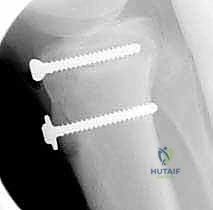

5. التثبيت الداخلي (Internal Fixation)

هنا تبرز مهارة الجراح في اختيار طريقة التثبيت التي لا تضر بصفيحة النمو (إذا كانت لا تزال مفتوحة).

* استخدام البراغي المجوفة (Cannulated Screws): يتم إدخال سلك توجيهي رفيع أولاً، وبعد التأكد من موقعه بالأشعة السينية داخل غرفة العمليات، يتم إدخال برغي أو برغيين من التيتانيوم القوي فوق السلك لتثبيت العظم. يحرص الدكتور هطيف على توجيه البراغي من الأمام إلى الخلف، وفي بعض الأحيان بزاوية مائلة لتجنب اختراق صفيحة النمو قدر الإمكان.

* شريط التوتر السلكي (Tension Band Wiring): في بعض الحالات التي يكون فيها الكسر مفتتاً أو القطعة العظمية صغيرة جداً، قد تُستخدم أسلاك معدنية قوية تُلف حول البراغي ووتر الرضفة لتوفير ضغط ديناميكي يساعد على الالتئام السريع.